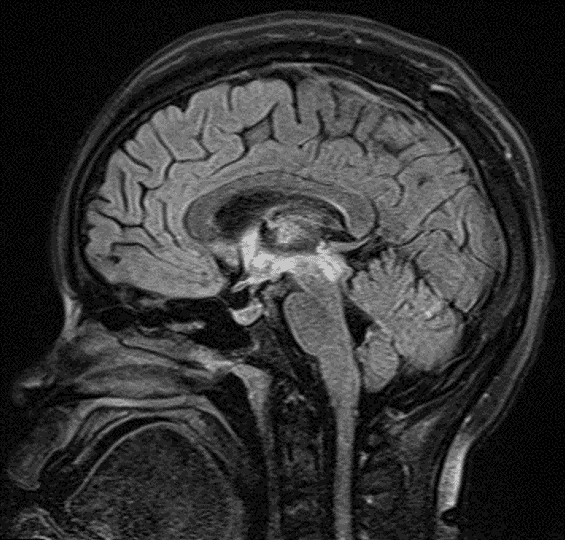

• T2/FLAIR signal hyperintensity in the right greater than left thalami and right greater than left dorsal midbrain with involvement of the periaqueductal gray matter, hypothalamus, anterior commissure, and mamillary bodies

FLAIR signal hyperintensity along the ependymal margins of the third ventricle and cerebral aqueduct, extending into the right greater than left thalami.